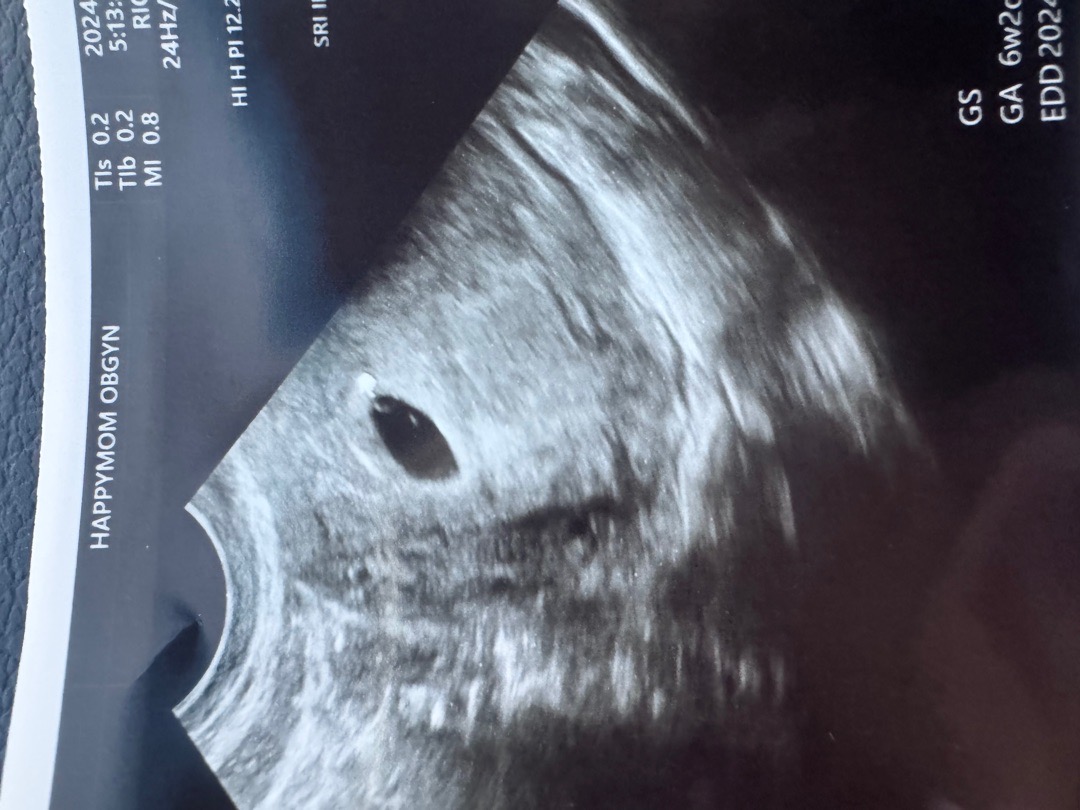

네...ㅠ 아기집, 이쁜 링모양 난황, 난황옆 아기까지 보이는데 정상수준의 절반크기라고 하시더라구요..ㅜㅜ 제발 수정과 착상이 늦어진것이길..... 문제없기를 바랍니다ㅠ

흐릿한 난황 그리고 2개..

6주차 흐릿한 난황.. 또 하나는 뭐죠… 너무 기대하지말고 일단 20-30프로는 유산생각하라고ㅜ했는데 저랑 같은사례있으신가요 ㅠㅜㅠ 또 일주일을 어케기다리죠 ㅜㅜㅜ